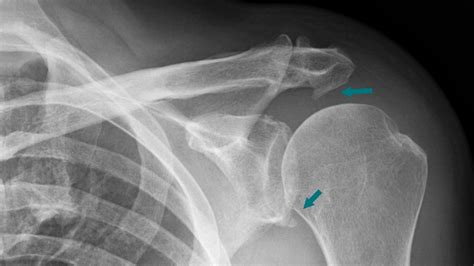

If you suspect a bone spur shoulder, seeking professional medical advice is essential. A doctor will typically perform a physical examination to test the range of motion and identify areas of tenderness. To confirm the diagnosis, they may use:

• X-rays: These are excellent for visualizing bone growths and seeing the spacing within the joint.

These spurs most commonly form on the acromion, the top part of the shoulder blade. When they form here, they can narrow the subacromial space—the area through which the rotator cuff tendons pass—leading to shoulder impingement syndrome. This condition is essentially a structural conflict where the bone is physically impeding the smooth mechanics of the shoulder joint.